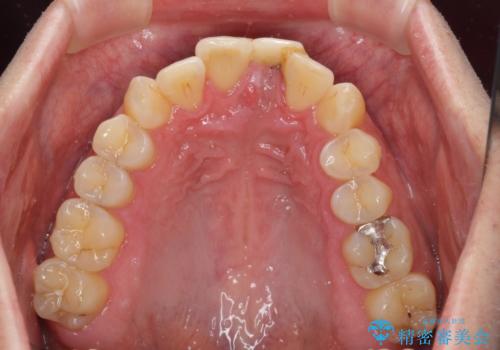

インプラントが唇側に埋入されており、セラミッククラウンの歯肉ラインが左右非対称となっていました。

仮歯は両サイドの歯と接着剤で止められており、接着が著しく変色していたため、セラミッククラウンが装着されて自然な口元となりました。